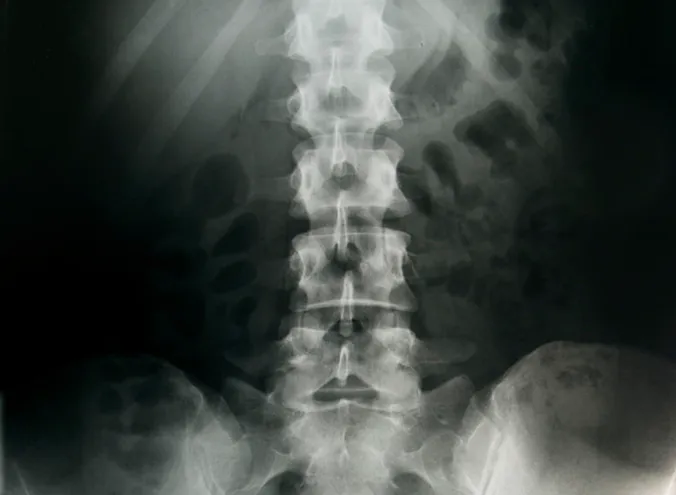

- Spinal Adjustments and Manipulations: Utilizing various techniques, Dr. Perlman performs precise adjustments to correct spinal misalignments, restore proper joint motion, and alleviate nerve interference, which are often at the core of back and neck pain.

- Lower Back Pain Treatment: Specializing in alleviating chronic and acute lower back pain, Dr. Perlman develops tailored treatment plans to provide relief and prevent future occurrences, focusing on both immediate comfort and long-term stability.

- Neck Pain Management: Addressing issues ranging from stiffness and limited range of motion to more severe neck discomfort, his treatments aim to reduce pain and improve flexibility in the cervical spine.